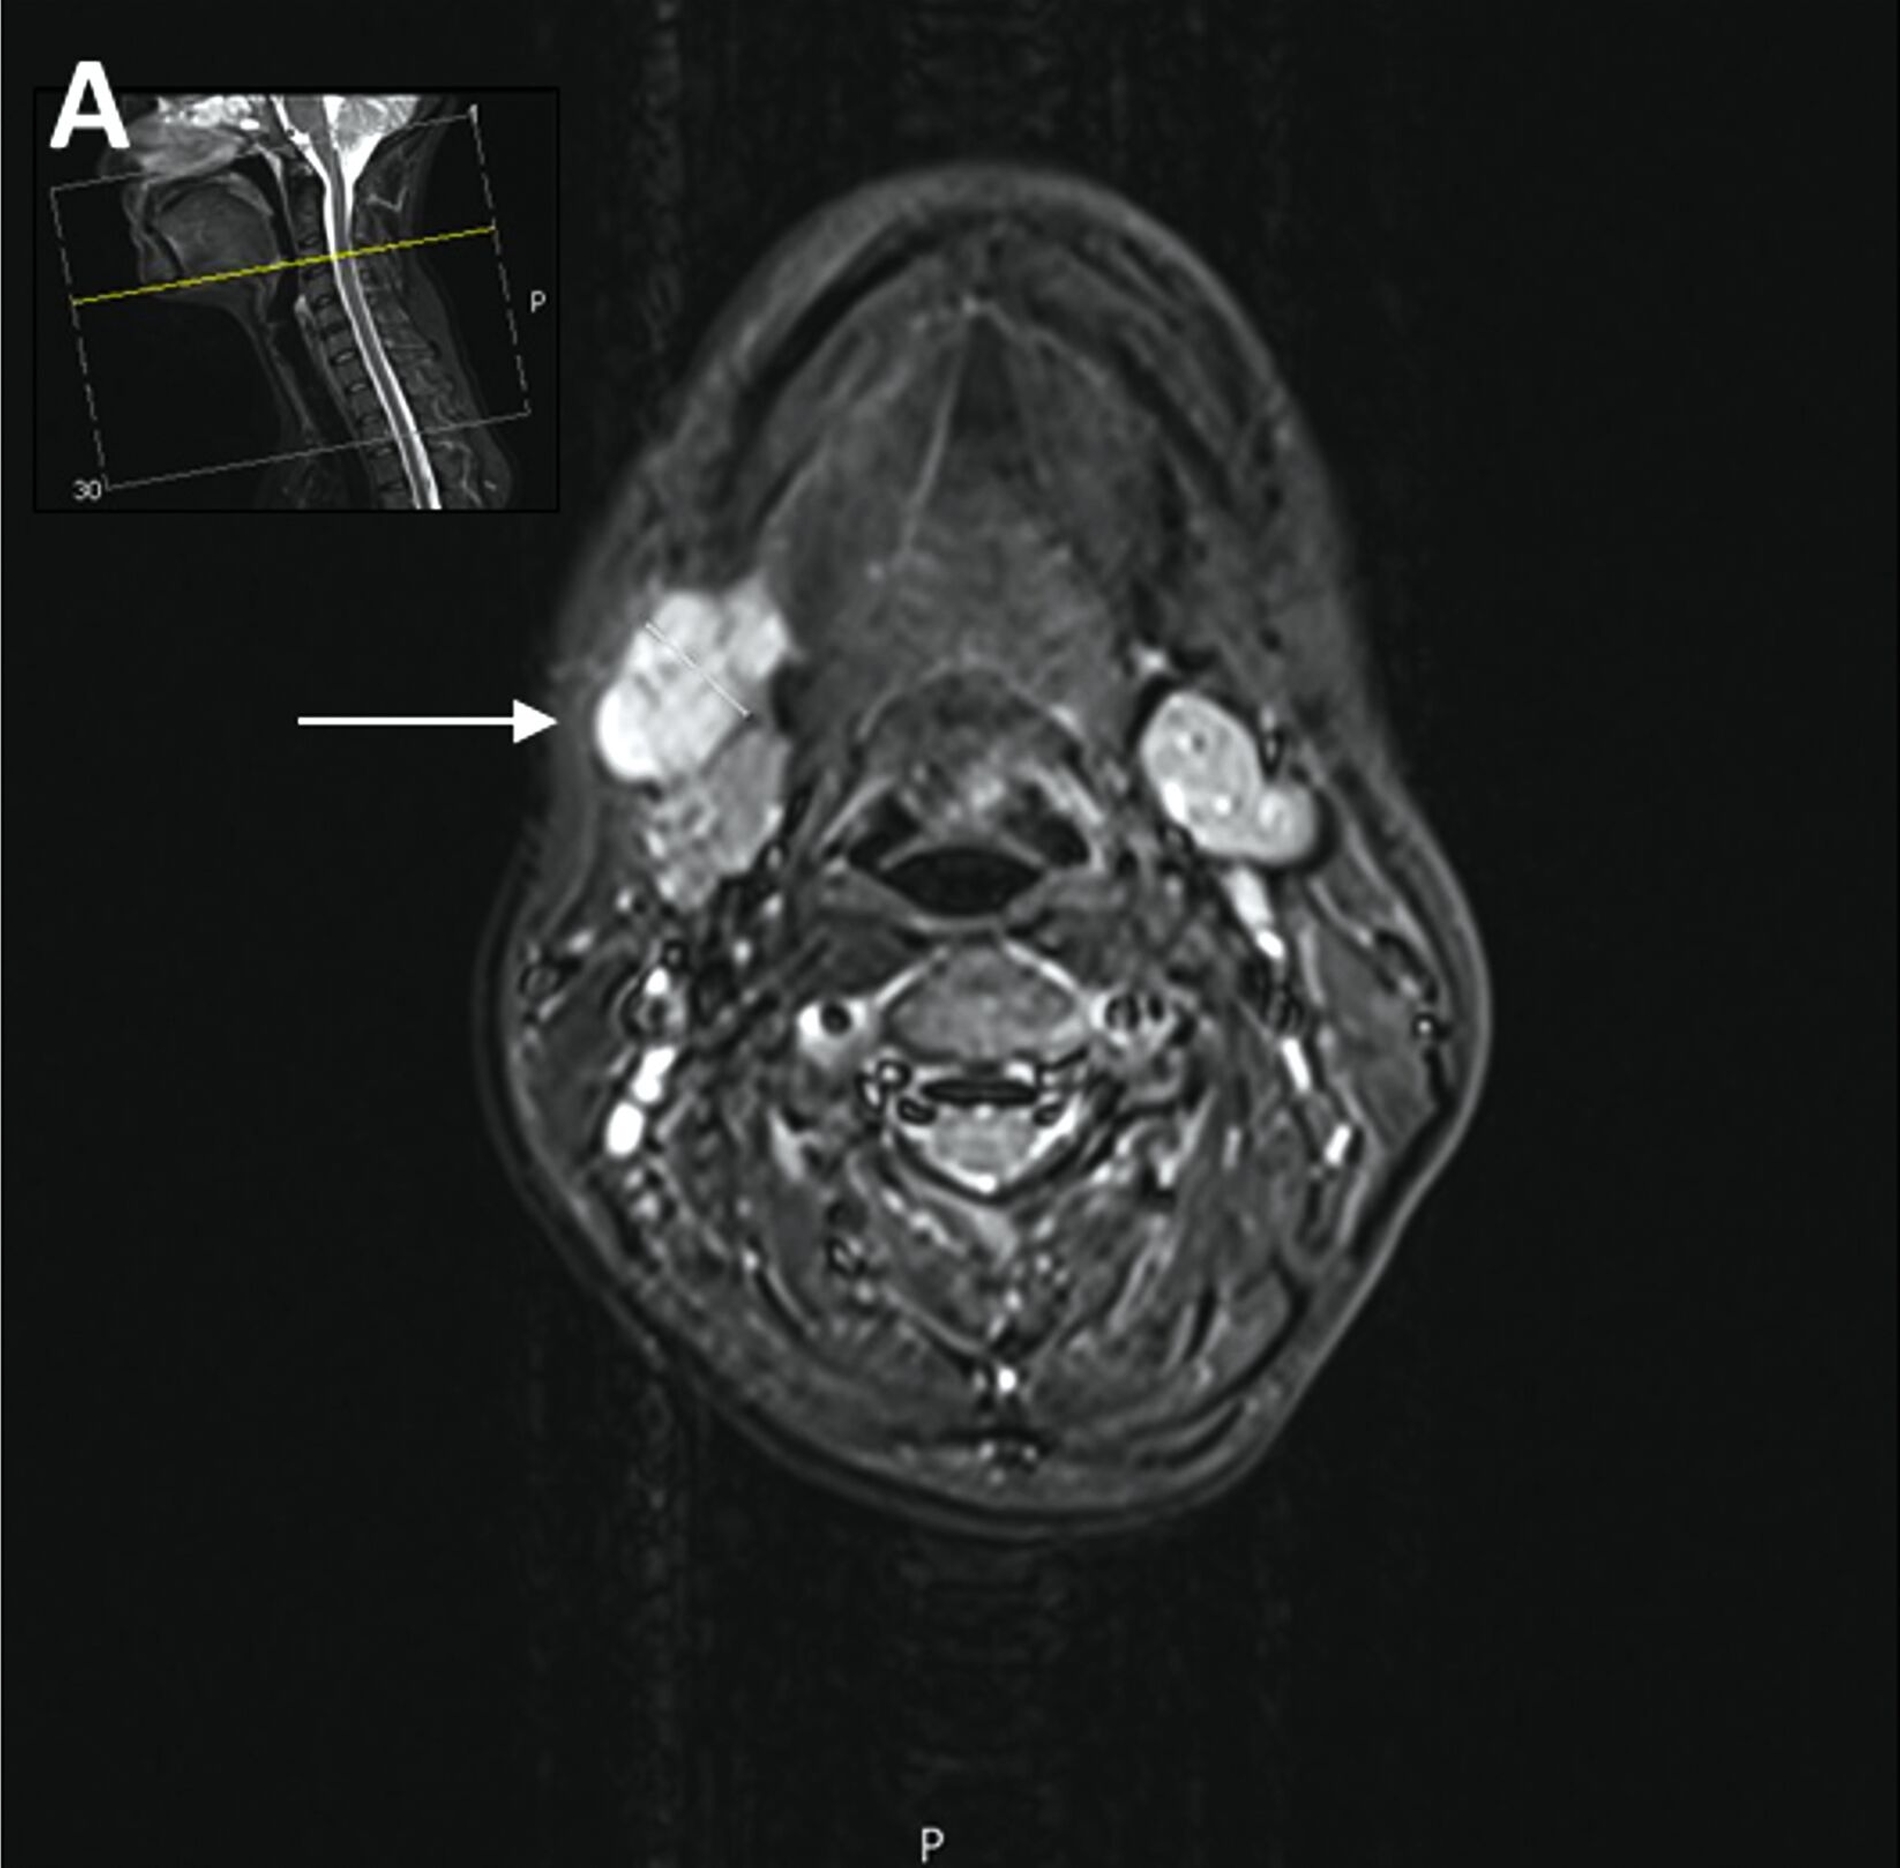

Trotz vorübergehender Remission kam es im August 2023 zu einem erneuten Krankheitsfortschritt mit dem Auftreten eines Metastasen-suspekten Lymphknotens im rechten Halsbereich (Abbildung 1). Bei der chirurgischen Entfernung (Abbildung 2) sowie der histologischen und molekularpathologischen Untersuchung wurde ein kleinzelliges neuroendokrines Lungenkarzinom nachgewiesen (Abbildung 3). Zusätzlich wurden genetische Analysen durchgeführt, die verschiedene Genmutationen und eine Fusion von CTNND1:KMT2A ergaben. Die Therapieentscheidungen basieren derzeit auf den Ergebnissen der molekularen Tumorboarddiskussion.